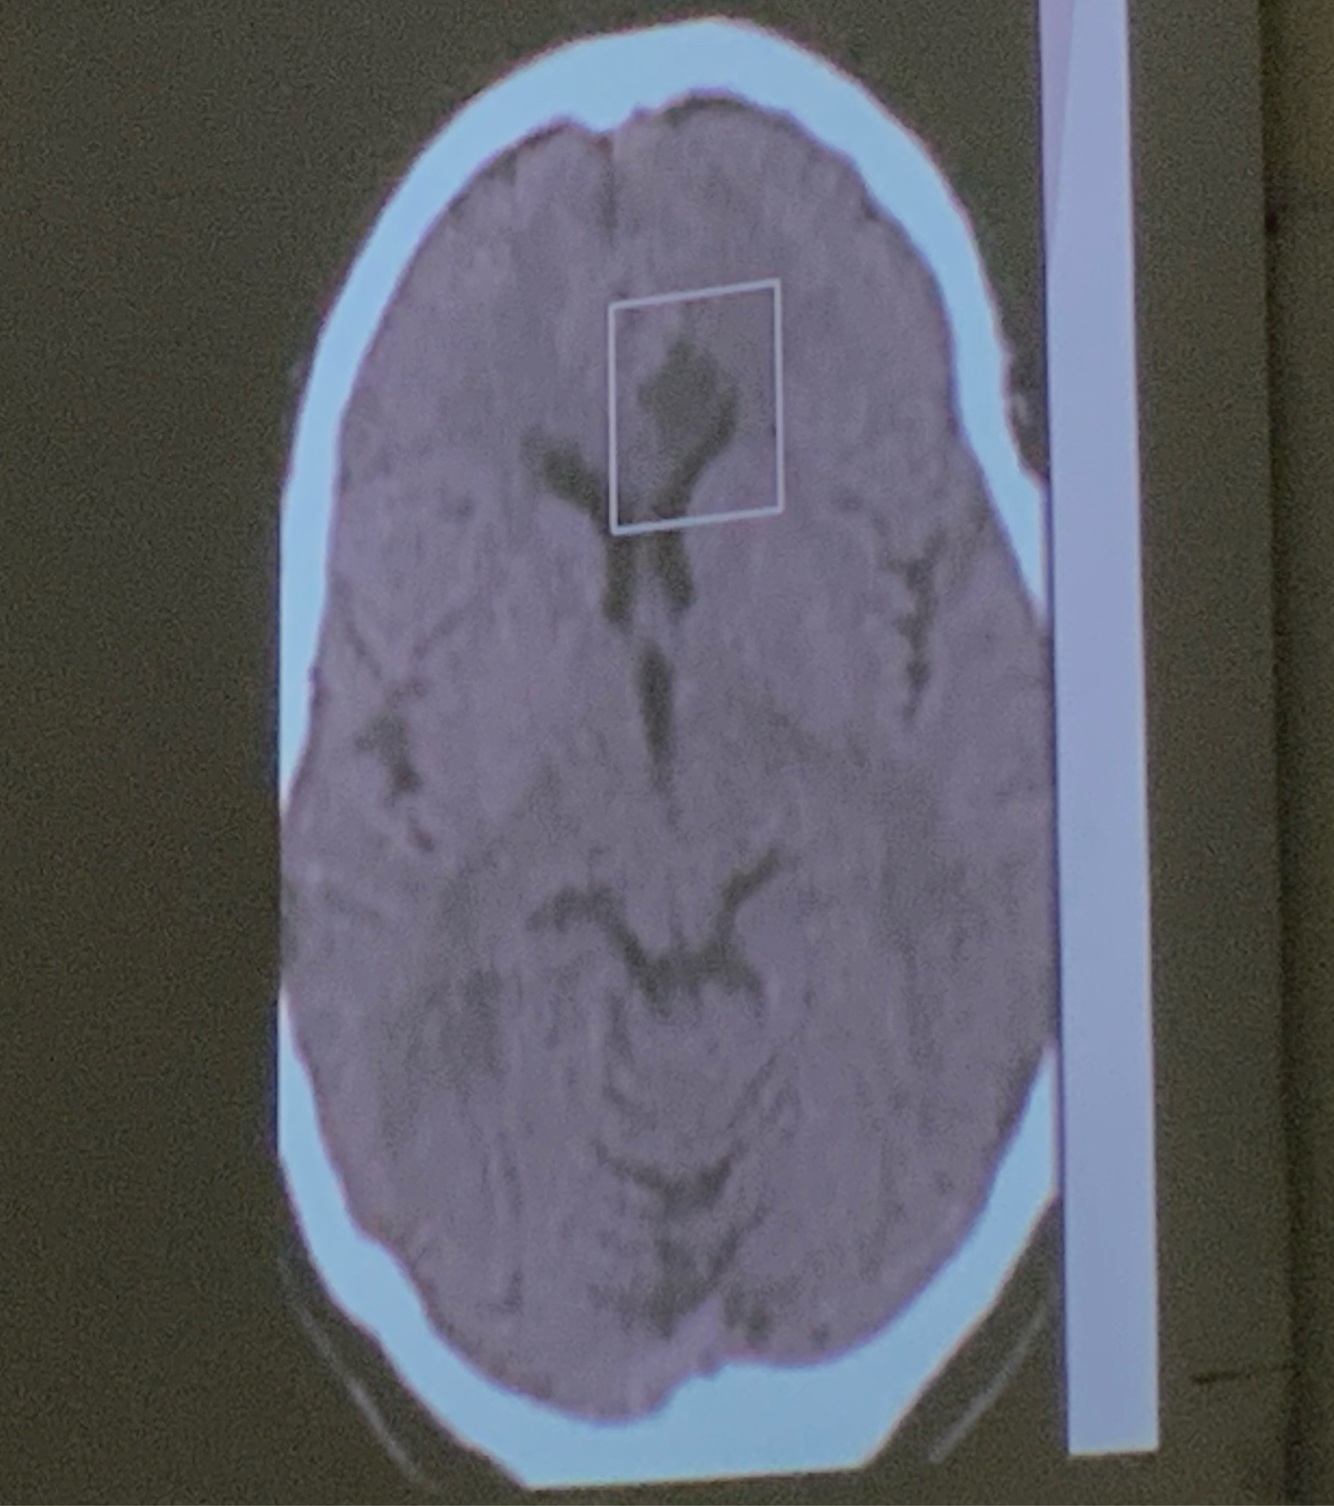

11

Q

Que arteria se encuentra afectada

A

ACA